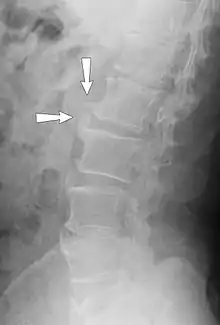

Osteophytes form naturally on the back of the spine as a person ages and are a clinical sign of degeneration in the spine. In this case, the osteophytes are commonly not the source of back pains, but instead are a sign of an underlying problem. However, osteophytes on the spine can impinge on nerves that leave the spine for other parts of the body. This impingement can cause pain in both upper and lower limbs and a numbness or tingling sensations in the hands and feet because the nerves are supplying sensation to their dermatomes.[6]